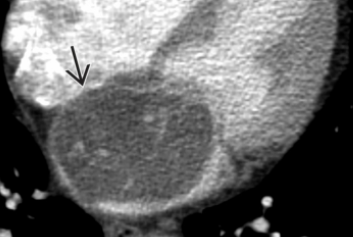

CT

- Masse ovalaire du septum inter-atrial

- Pédicule court à large base

- Hypodense (plus hypodense que le sang natif ou le myocarde)

- Prise de contraste hétérogène

- Protrusion dans la lumière